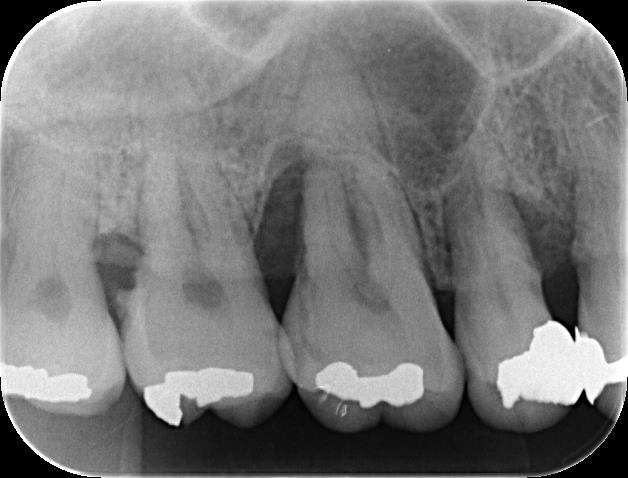

エックス線写真からは、歯石の沈着が著しく、歯槽骨の吸収も進行しているのが確認できます。

下のエックス線写真は、再生療法後、6~9ヵ月経過したものです。

歯槽骨の吸収が進行していた部位の改善が認められます。